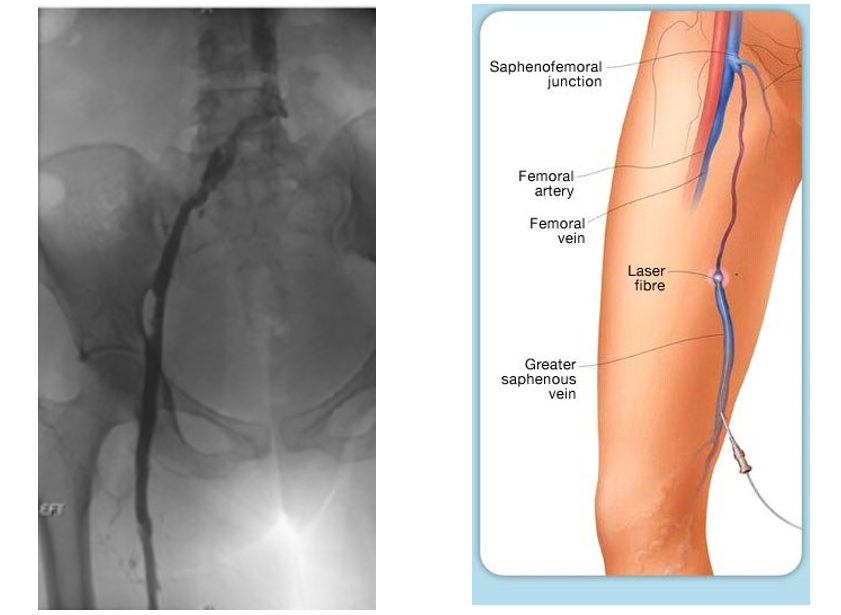

– Radiofrecuencia o Energía Láser (Ablación): Se introduce un tubo delgado (catéter) a través de las venas más anchas. El calor emitido por el catéter hace que la vena se cierre, haciendo que desaparezca la vena varicosa.

En el tratamiento con láser para las venas pequeñas, se envía pulsos de luz sobre la vena, lo que hace que ésta desaparezca lentamente. No se utilizan incisiones ni agujas.